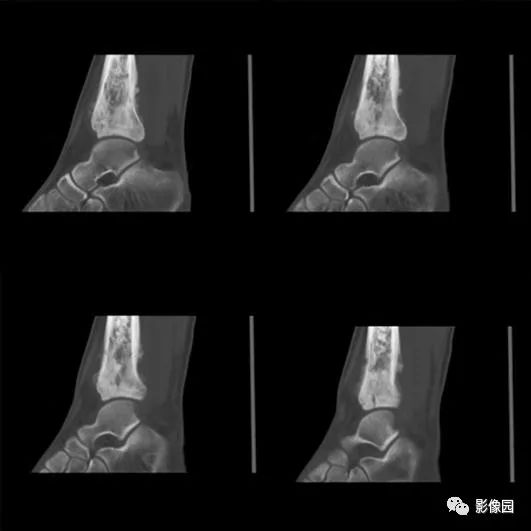

评论:前片X线示左胫骨下段及干骺端病变,髓腔内密度不均匀增高,内侧骨皮质可见骨质破坏,可见骨膜反应。CT示病灶内见多发斑片状肿瘤骨(黄色箭头),周围可见针状骨膜反应(红色箭头)。周围软组织肿胀。MRI示胫骨下段以长T1、长2信号为主的混杂信号影,未跨越胫距关节面,周围未见明显软组织肿块。周围软组织广泛片状长T1长T2信号影。复查X线示病变较前片明显进展,左侧胫骨远段及干骺端骨质破坏,周围可见针状骨膜反应及Codman三角(蓝色箭头)形成。相邻左侧腓骨下端、距骨滑车受累。

【结果】术中所见:左胫骨远端骨膜明显增厚,周围可见鱼肉样软组织,骨表面少许破坏,骨质条件差,进入骨髓腔后可见少许髓腔内少许白色软组织。切除骨膜、骨髓腔内组织送病检。

绝大多数骨肉瘤可依据X线平片确立诊断,但CT或MRI是必不可少的补充。MRI能清楚了解肿瘤侵及的范围,提供肿瘤周围血管、神经、肌肉受累的信息,有利于治疗方案的确立。CT除了与MRI一样有利于发现平片上不易显示部位的病变外,由于其对细小骨化和钙化敏感,当平片上不能肯定有无瘤骨或瘤软骨钙化时,CT对确定骨肉瘤的诊断有重要意义。